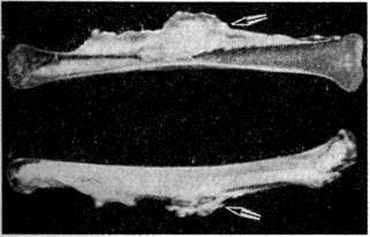

Макроскопически патологический процесс имеет вид костного утолщения (гиперостоза), которое при локализации на длинных трубчатых костях (бедренная, большеберцовая, плечевая) как бы стекает сверху вниз с образованием характерных напластований, напоминающих наплывы горящей свечи (рисунок 1).

На рентгенограмме видны участки резко уплотнённой структуры, расположенные так, что создаётся впечатление о якобы происшедшем «стекании» остеосклеротических масс кости с вышерасположенных на нижерасположенные отделы. Поражаются преимущественно длинные и короткие, а также мелкие кости конечности (рисунок 3), реже лопатки и тазовые кости. Уплотнение структуры наблюдается не на всем протяжении поражённой кости, а на определённом её участке, преимущественно эксцентрично. Помимо склерозирования губчатого вещества кости, при Мелореостоз нередко наблюдается гиперостоз поражённых костей. В длинных и коротких трубчатых костях он проявляется в виде односторонне ассимилированных периостальных наслоений, утолщающих и деформирующих диафиз. При длительном наблюдении иногда обнаруживается нарастание протяжённости и выраженности остеосклероза (смотри полный свод знаний), гиперостоза (смотри полный свод знаний) и деформации.